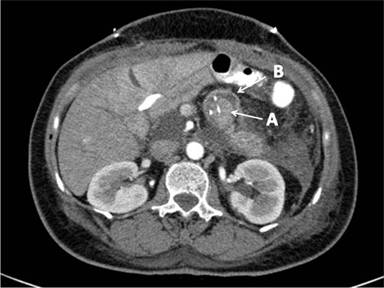

We would like to share with the readers interesting computerized tomography (CT) images of a pancreaticojejunostomy fashioned by a telescopic invagination anastomosis between the remnant of the pancreas and a loop of the small bowel.

Image 1 is a double-contrast CT scan carried out during the arterial phase, showing a coronal slice of the pancreaticojejunostomy with a silicon cannula in the duct of Wirsung. The proximal end of the remnant pancreas (A) was invaginated in a loop of the small bowel (B). Some haziness of the surrounding fat and a small amount of free fluid is also depicted which is compatible with the postoperative phase.

Image 1 |